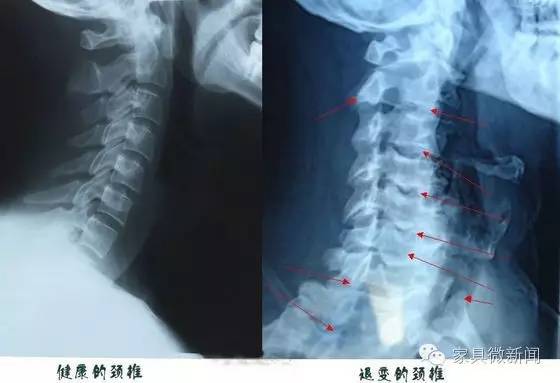

而相比床垫的丰富,枕头这一重要的睡眠产品却显得相对黯然,在枕头与床垫的搭配中,床垫的角色更趋重于对腰椎等身体躯干的保护,而枕头则更多的起到了保护颈椎平衡肩部的作用。实际上,至2016年,我国大约有1.5亿人患有颈椎病,平均概率超过了10%,50岁以上的患病概率达到25%,且有逐年年轻化的趋势,另外,从颈椎的解剖和生理角度来看,颈椎较腰椎的灵活度要大,活动频率也高,而颈椎的支持结构却较腰椎薄弱。所以,颈椎的保护意义甚至比腰椎更为重大,而这一切与拥有一个好的枕头是密不可分的。